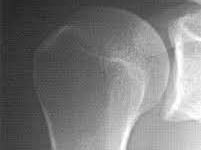

🔸 회전근개 질환

회전근개에 염증이 생기거나, 퇴행성 변화로 인해 파열되는 경우입니다. 팔을 들거나 뒤로 돌릴 때 통증이 심해집니다.